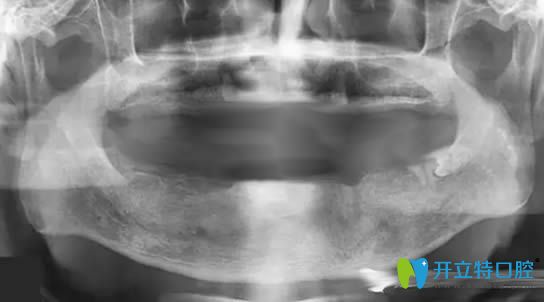

帶10年活動(dòng)假牙萎縮的牙槽骨圖片

但好景卻不長(zhǎng),在2025年的時(shí)候,總出現(xiàn)黏膜潰瘍等牙周病,我讓反復(fù)的到口腔進(jìn)行治療......讓我的飲食成了的問題。為了改善現(xiàn)狀,孩子帶我去了一家私人牙科進(jìn)行咨詢,說我佩戴活動(dòng)假牙時(shí)間長(zhǎng)了,造成了牙槽骨低平,無(wú)法讓活動(dòng)義齒取得好的固位,并且,就連做種植牙的基礎(chǔ)條件都沒有了......

牙槽骨萎縮全景片